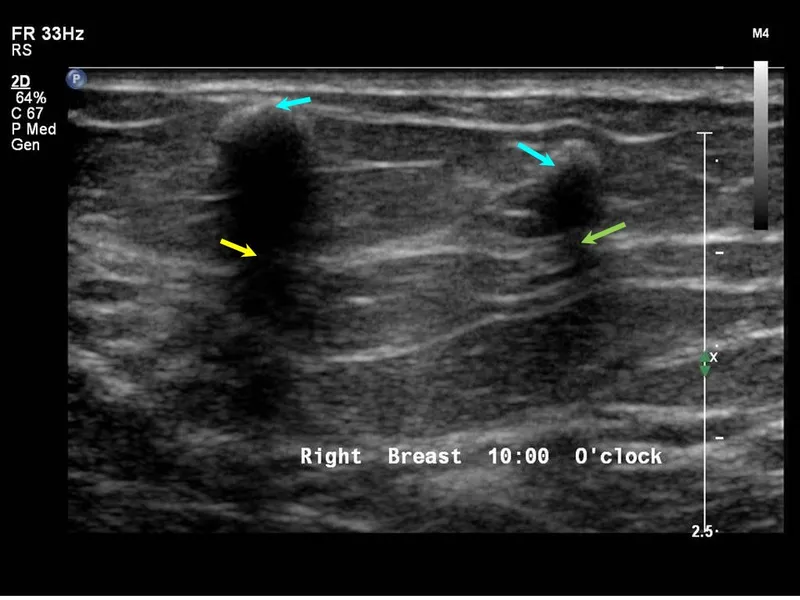

- Anechoic: Pure black (e.g., simple fluid, cysts). No reflection.

- Posterior Acoustic Enhancement: Bright area behind a fluid-filled structure (e.g., cyst) as sound travels with less resistance.

| Acoustic Enhancement | Increased signal intensity deep to a weakly attenuating structure (e.g., cyst). | 💡 Classic sign of a simple fluid-filled cyst (e.g., in breast, ovary, kidney). |

⭐ Acoustic enhancement (posterior enhancement) is a crucial feature used to characterize fluid-filled structures like simple cysts, distinguishing them from solid masses which typically cause shadowing or have no effect.